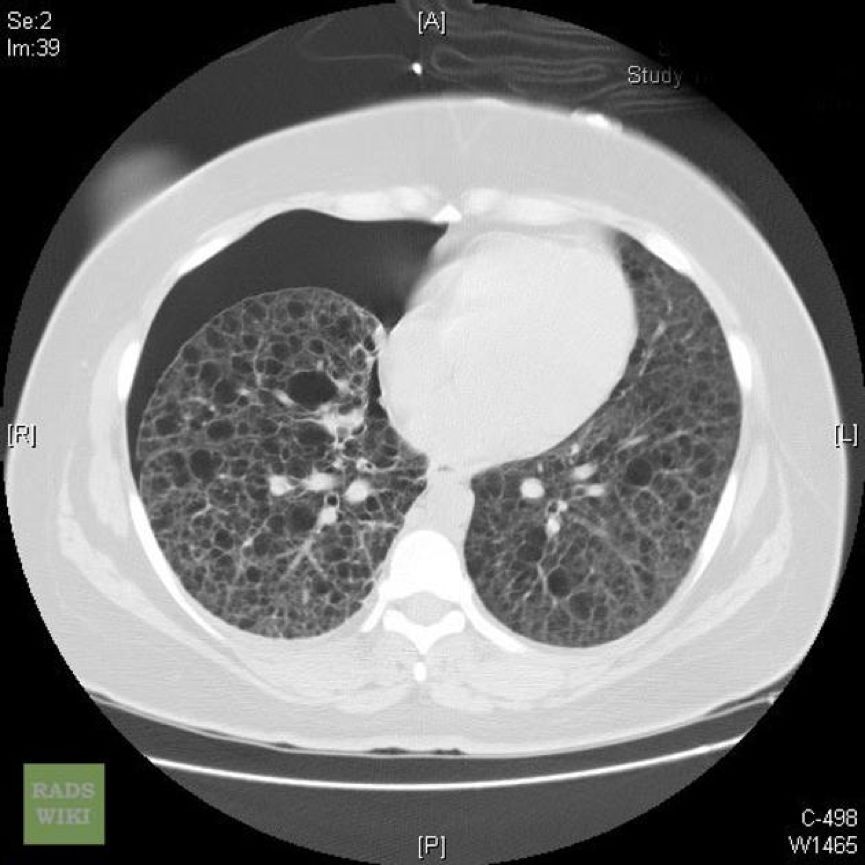

外院肺功能检查提示:阻塞性通气功能障碍。HRCT显示双肺弥漫性分布类圆形薄壁囊状阴影,囊壁较光滑,囊腔大小不等,多数在2~10 mm之间,右侧胸腔内见气体影。纵隔结构清楚,未见肿大淋巴结。

常规CT表现为两肺密度减低,体积增大,呈肺气肿样改变。HRCT对本病的早期诊断及病情发展的监测有重要意义,其特征性改变为两肺广泛弥漫性分布的薄壁小囊状病变,两侧对称,无上中下肺野的区别,也无中央性与周围性的分布差异。囊腔直径为2~30 mm,大多数直径小于10 mm,囊壁厚度多小于2 mm。